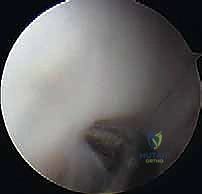

الخطوة 3: الاستكشاف التشخيصي (Diagnostic Sweep)

يتم إدخال المنظار لفحص المفصل بالكامل من الداخل. يتم تقييم حالة الغضروف، البحث عن أي أجسام حرّة مختبئة، وتقييم مدى تلف الرأس الصغير (Capitellum).

- أ. إزالة الأجسام الحرة وتنظيف المفصل (Debridement):

إذا كانت القطعة منفصلة تماماً وميتة ولا يمكن إنقاذها، يتم استخراجها بالكامل لمنعها من تدمير بقية المفصل. يتم تنظيف حواف